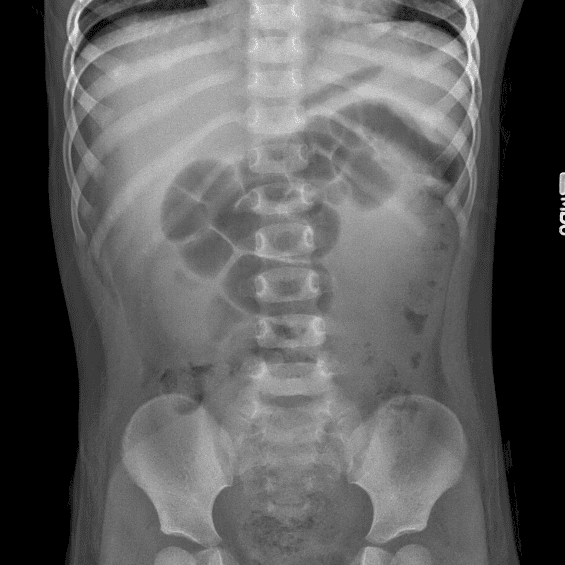

Peds Abdomen

Practice

Simulates call by including subtle or difficult cases and some normals.

30 cases